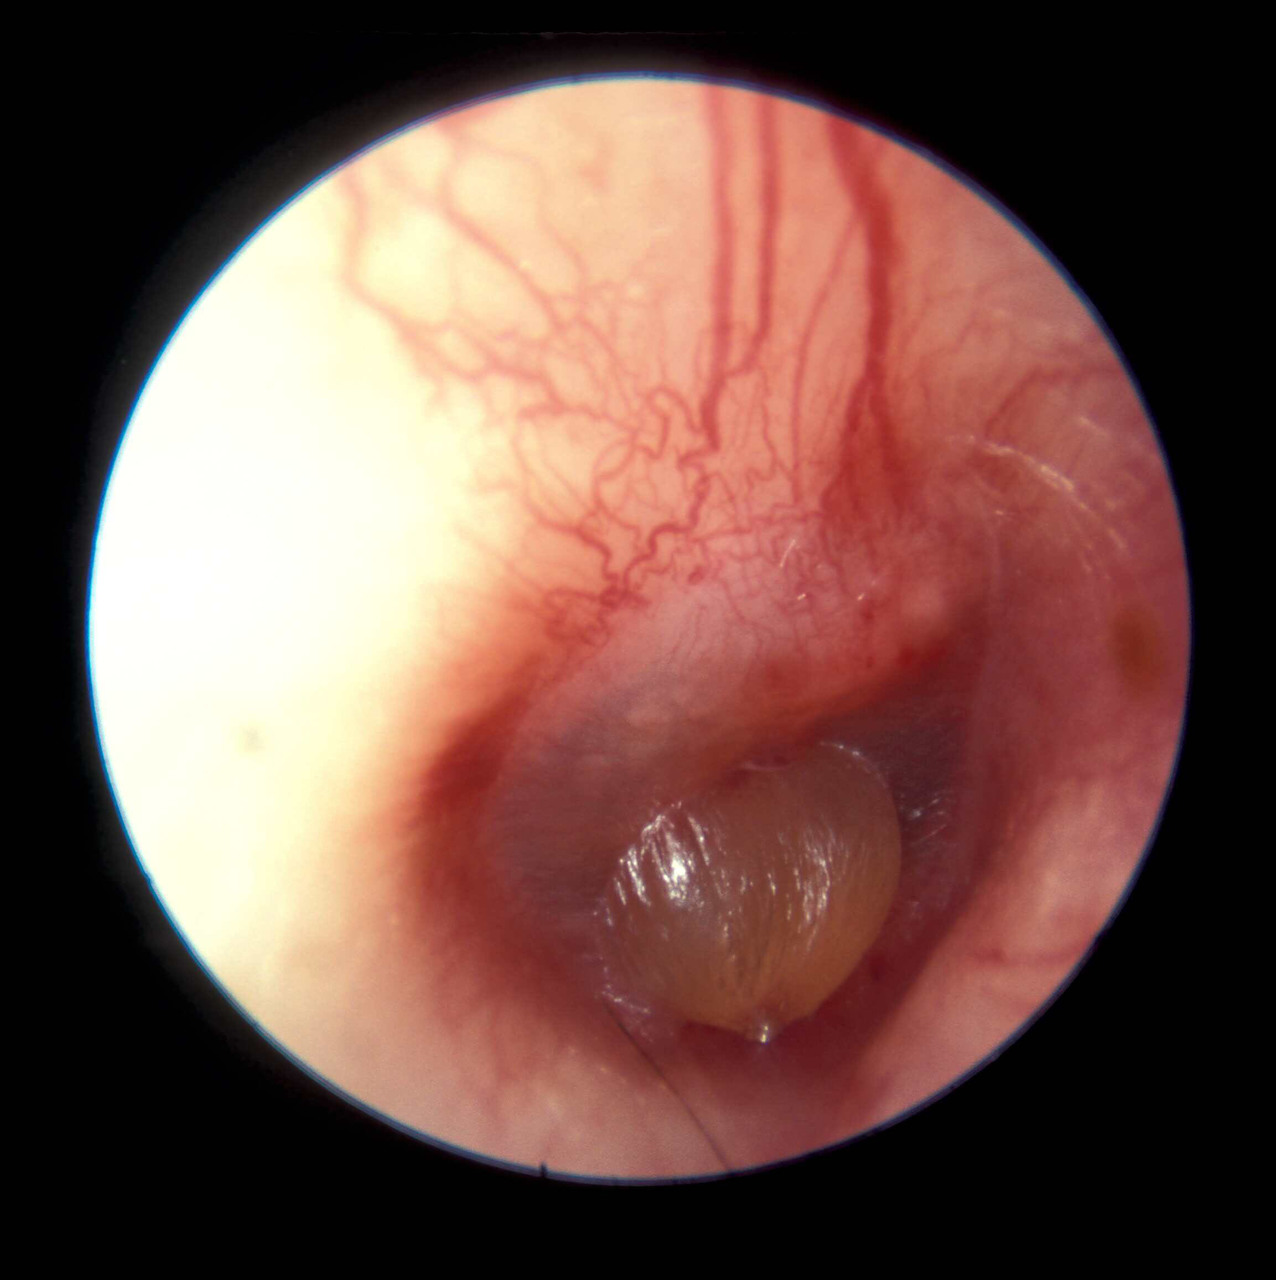

Vous faites un examen du tympan droit. Vous trouverez ci-dessous plusieurs exemples d'otoscopies. Figure 6

Figure 7

Figure 8

Figure 9

Figure 10

Question 8 - Dans le cas d’une fracture du rocher à droite, quelle(s) est (sont), parmi les otoscopies présentées ci-dessus, celle(s) qui est (sont) compatible(s) avec ce diagnostic à 24 heures du traumatisme ?

Tympan normal : la fracture peut ne pas concerner l’oreille moyenne et ne pas entraîner de saignement

Poche de rétraction avec atélectasie postérieure : il s’agit dans ce cas d’une pathologie chronique du tympan, sans rapport avec la fracture du rocher

Otite moyenne aiguë : ce n’est pas le tableau (absence de fièvre), d’autant que le délai est trop bref pour avoir une complication infectieuse

Hémotympan : visualisation d’un hématome dans l’oreille moyenne. C’est l’image typique dans le contexte de fracture du rocher

Myringite bulleuse : c’est ici une complication infectieuse avec la constitution d’une bulle intra-tympanique

Dans un contexte de fracture du rocher, soit le tympan peut être normal, soit le plus souvent il y a un saignement dans l’oreille moyenne et on constate un hémotympan. Cliniquement, l’hémotympan se comporte exactement comme une otite séromuqueuse (présence de liquide dans l’oreille moyenne), cf. les questions suivantes.